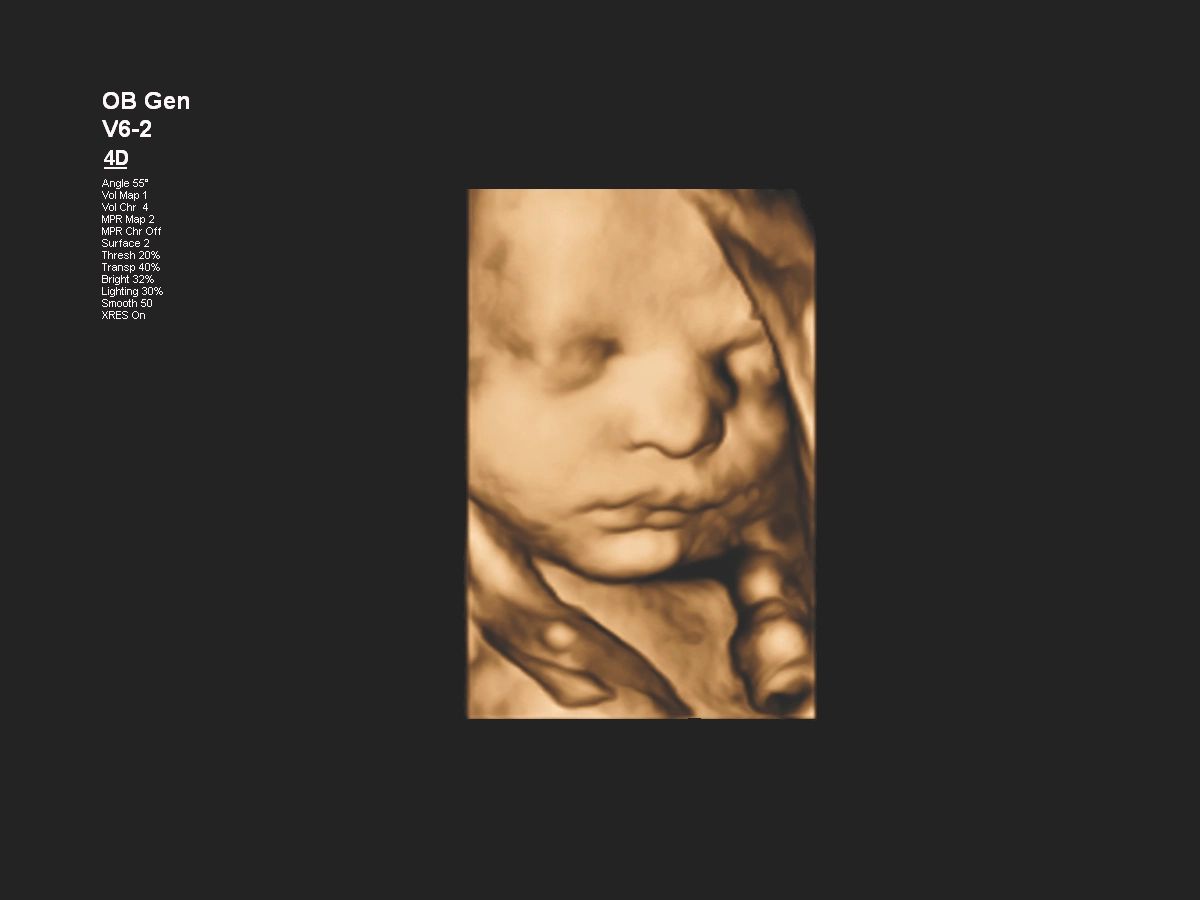

Функции для гинекологии и акушерства

- Free Hand 3D - возможность реконструкции 3D изображения при помощи линейного или конвексного датчика

- 4D Imaging - автоматическая визуализация 3D/4D изображения

- TrueVue - виртуальный источник света для получения качественного 3D/4D изображения

- FlexVue - опция для визуализации 3D изображений в плоскости

- aBiometry Assist - автоматические биометрические измерения

- Режимы 3D\4D для визуализации и анализа объемных данных